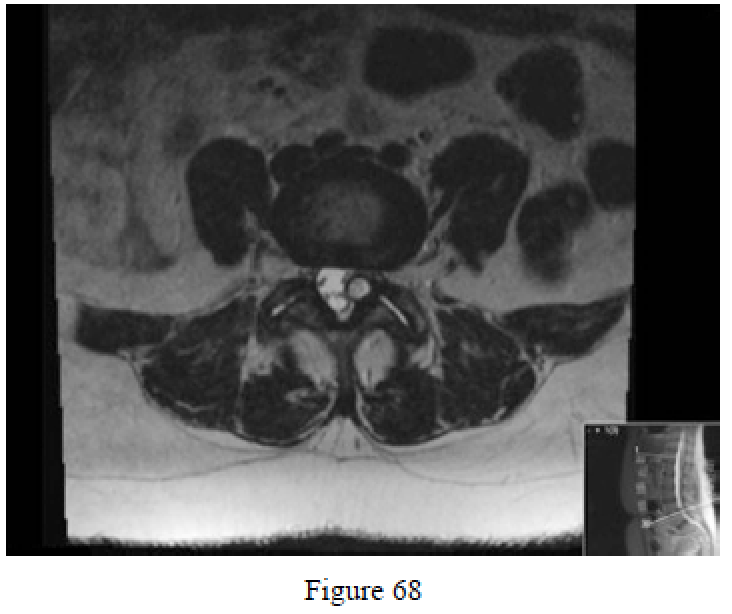

Question 68

Figure 68 is the MR image of a 53-year-old woman who has a 6-month history of left lower extremity radiculopathy. Before deciding upon surgical intervention, it is important to obtain